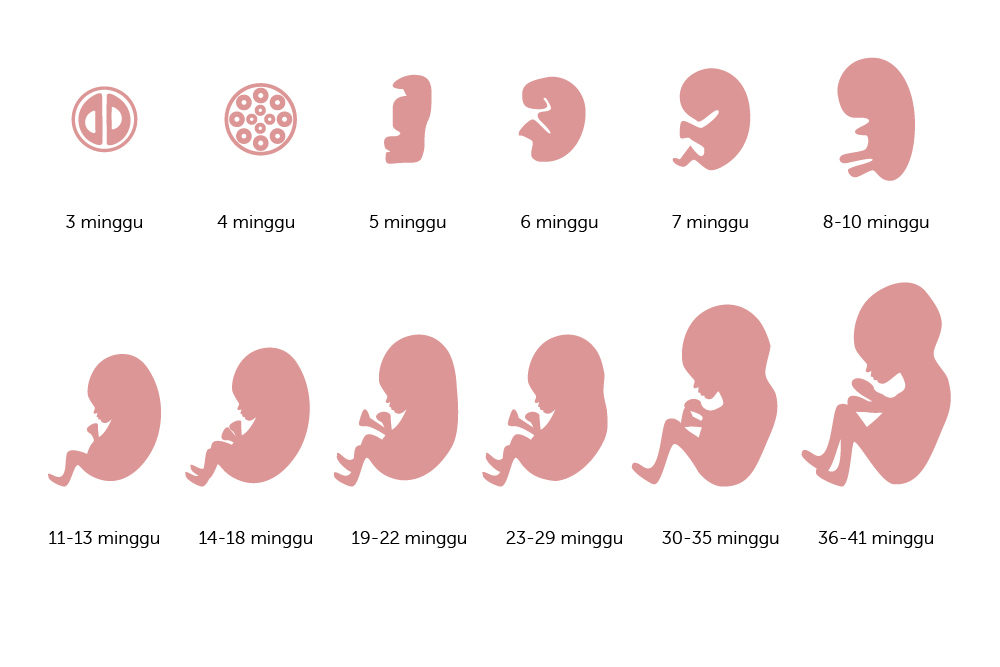

Perkembangan Janin Minggu ke Minggu 1-40 : Gambar Lengkap

Perkembangan Janin Minggu ke Minggu 1-40 : Gambar Lengkap

40 Minggu Tahap Perkembangan Janin di Rahim | Sharing di Sana

40 Minggu Tahap Perkembangan Janin di Rahim | Sharing di Sana

Ini Perkembangan Bayi dalam Kandungan dari Minggu ke Minggu - Alodokter

Ini Perkembangan Bayi dalam Kandungan dari Minggu ke Minggu - Alodokter